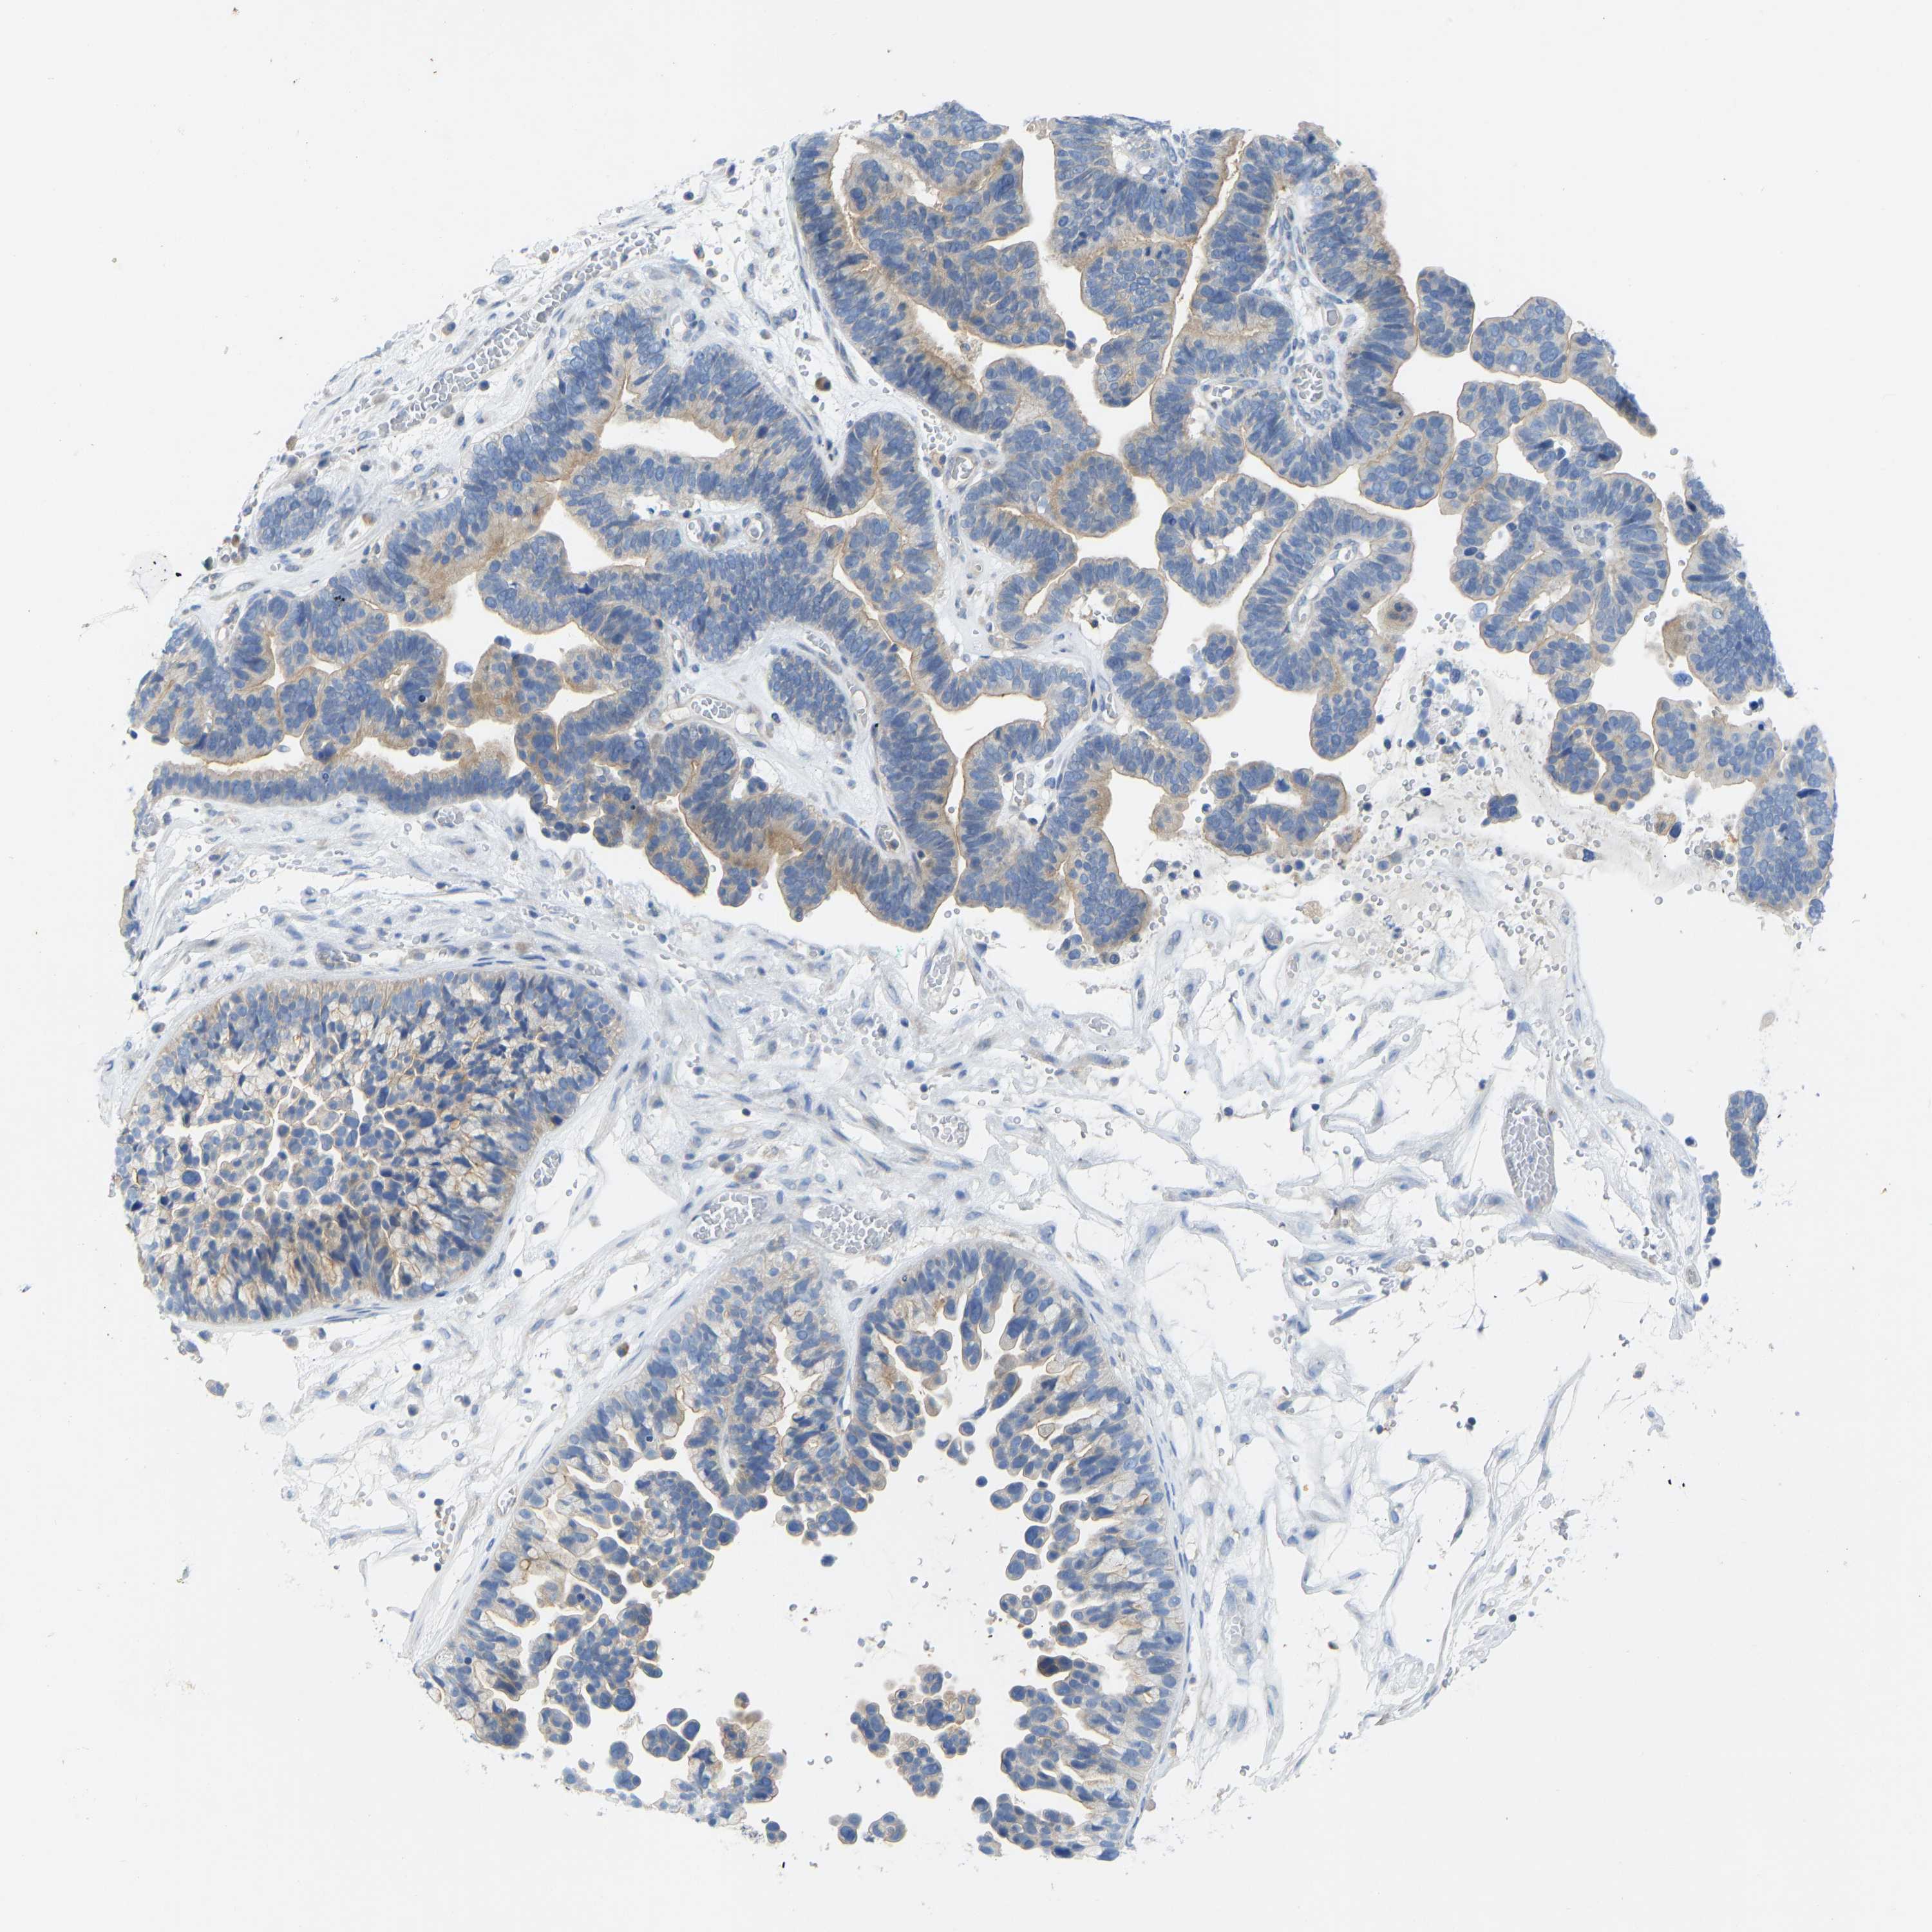

OVARIAN CANCER - Protein expressioni

A mouse-over function shows sample information and annotation data. Click on an image to view it in a full screen mode. Samples can be filtered based on level of antibody staining by selecting one or several of the following categories: high, medium, low and not detected. The assay and annotation is described here.

Note that samples used for immunohistochemistry by the Human Protein Atlas do not correspond to samples in the TCGA dataset.

Antibody stainingi

Antibody staining in the annotated cell types in the current human tissue is reported as not detected, low, medium, or high, based on conventional immunohistochemistry profiling in selected tissues. This score is based on the combination of the staining intensity and fraction of stained cells.

Each image is clickable and will lead to virtual microscopy that enables deeper exploration of all samples and also displays staining intensity scores, fraction scores and subcellular localization as well as patient and tissue information for each sample.

Antibody HPA012778

Antibody CAB018581

Staining

High

Medium

Low

Not detected

Intensity

Strong

Moderate

Weak

Negative

Quantity

>75%

75%-25%

<25%

None

Location

Nuclear

Cytoplasmic/membranous

Cytoplasmic/membranous,nuclear

Cystadenocarcinoma, serous, NOS

Carcinoma, endometroid

Cystadenocarcinoma, mucinous, NOS

Carcinoma, NOS